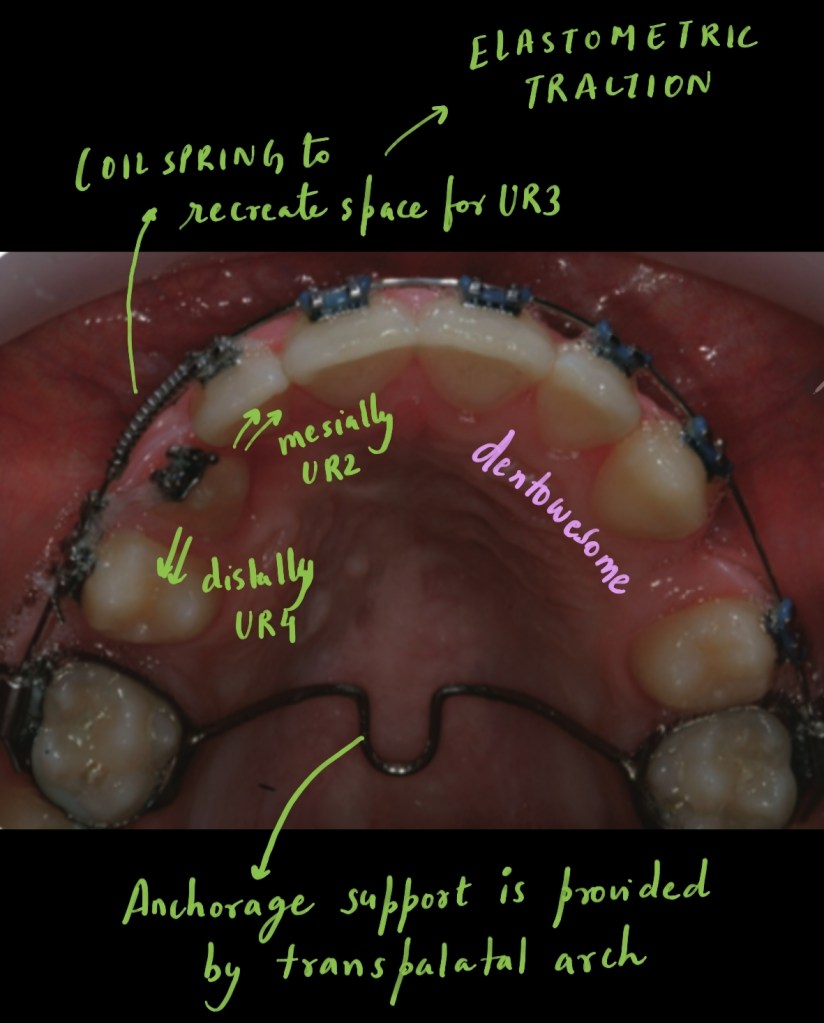

A 14-year-old male presented with a class I malocclusion on a skeletal class I base with average vertical dimensions complicated by an ectopic and mesially-angulated UR3, crowding of both arches and centre line discrepancies.

What will be the treatment for creating space for canine and correcting central line discrepancies? Which teeth will be extracted? What appliances will be used and what force level should be used during space closure?